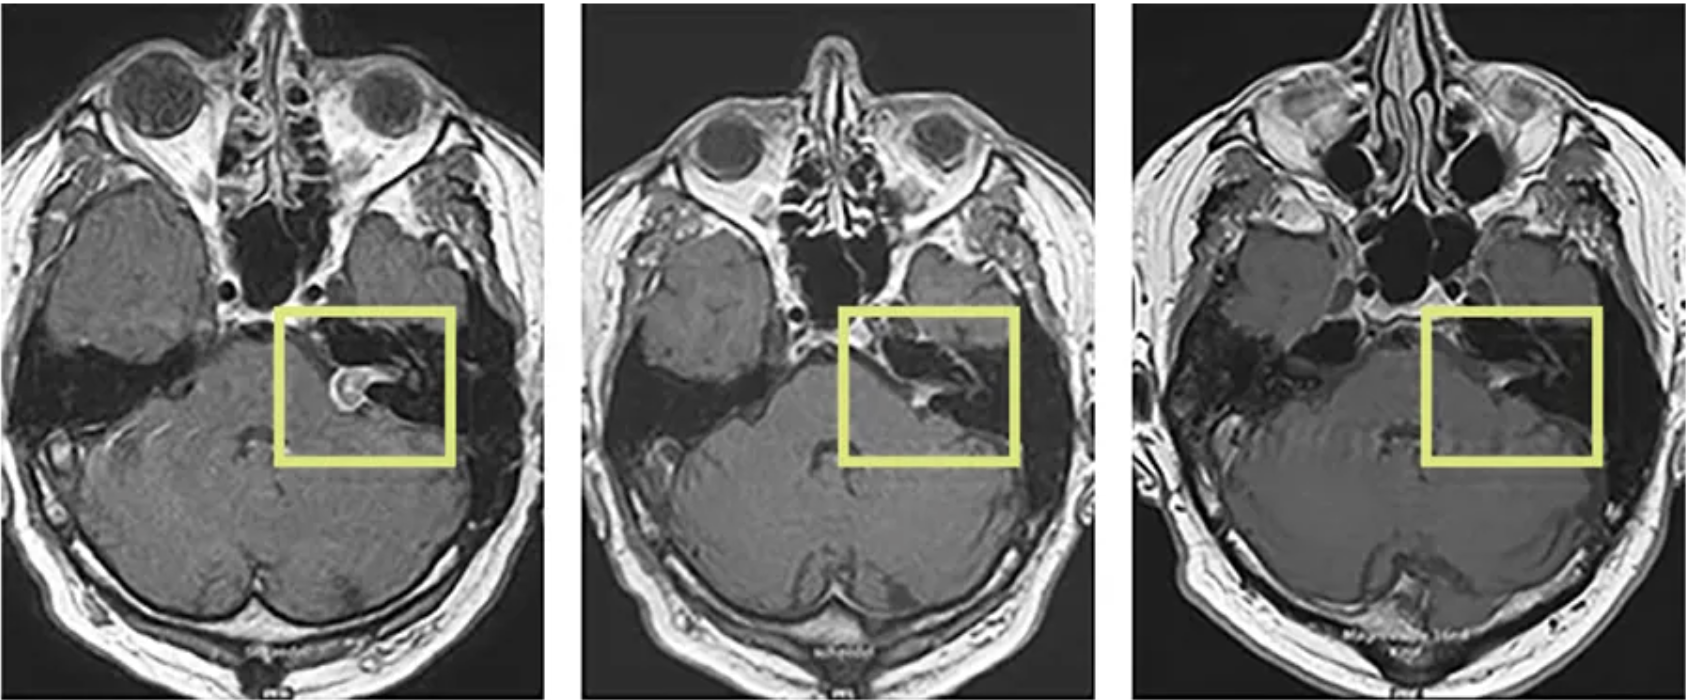

Beispiel einer CyberKnife-Therapie des Akustikusneurinoms im 6-Jahres-Verlauf

Die robotergeführte, radiochirurgische Behandlung hat den Effekt, dass Tumorzellen im Zeitverlauf absterben können. Im MRT ist das gut sichtbar: Im dargestellten Fall konnte mithilfe der CyberKnife-Therapie (2007) nicht nur das Tumorwachstum gestoppt werden, das Akustikusneurinom ist mit der Zeit auch deutlich geschrumpft (Bild Mitte 2009) und im weiteren Verlauf (2013) kaum noch zu sehen (rechts).